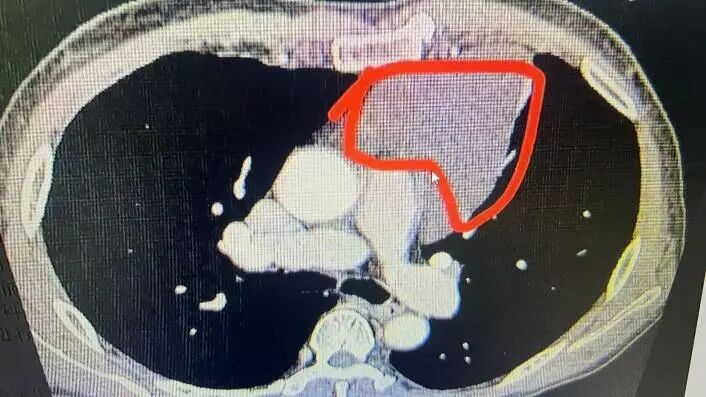

半个月前,患者李先生(化名)突发晕厥,被紧急送往潜江市中心医院胸外科就诊。经胸部CT检查发现,其前纵隔区域长有巨大肿瘤,医生诊断为前纵隔囊肿。该肿瘤紧邻心脏大血管,万幸的是,肿瘤与周边重要组织间尚存可操作间隙,为手术切除留下了希望。

手术当日,手术室氛围紧张而有序。当胸腔镜探入后,大家发现情况比预想的更复杂:肿瘤已压迫心包和肺组织,且与胸腔内多处组织粘连,同时紧邻心脏、主动脉、上腔静脉等关键结构,瘤体表面的血管如同藤蔓般密密麻麻地缠绕着,稍有不慎就可能引发大出血。